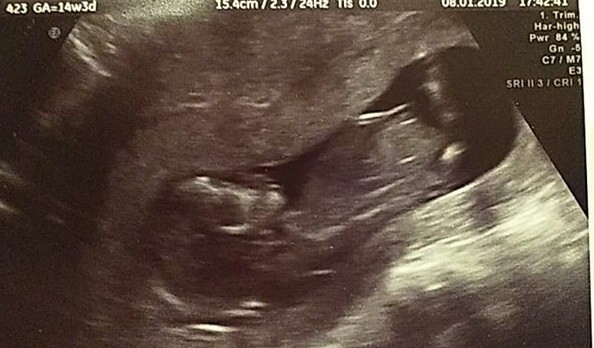

Hej :) a co powiecie u mni w 15tc było że dziewczynka w 19 było że chłopiec..do potwierdzenia na następnej wizycie..dodaje zdjęcia z ostatniego USG (19+3) może wy coś podpowiecie..dodam że na drugim zdjęciu to najjaśniejsze między nóżkami to pępowina..reszta??